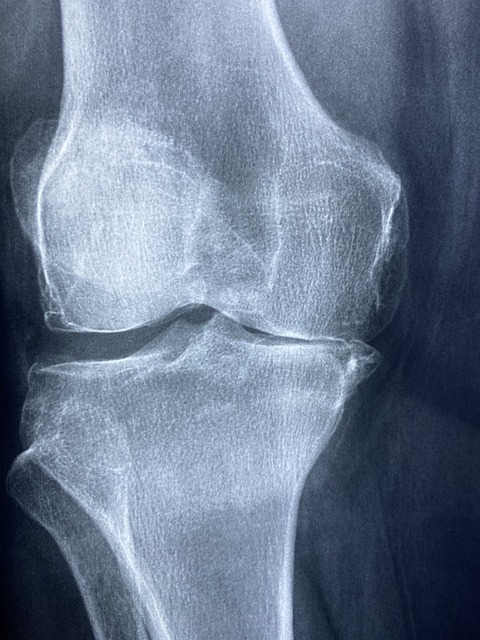

1. 골밀도 유지 및 골다공증 예방

MBP를 일정 기간 섭취하면 골밀도가 유지되거나 향상되는 결과가 관찰됩니다. 폐경기 여성이나 50대 이후 남성에게 특히 유용합니다.